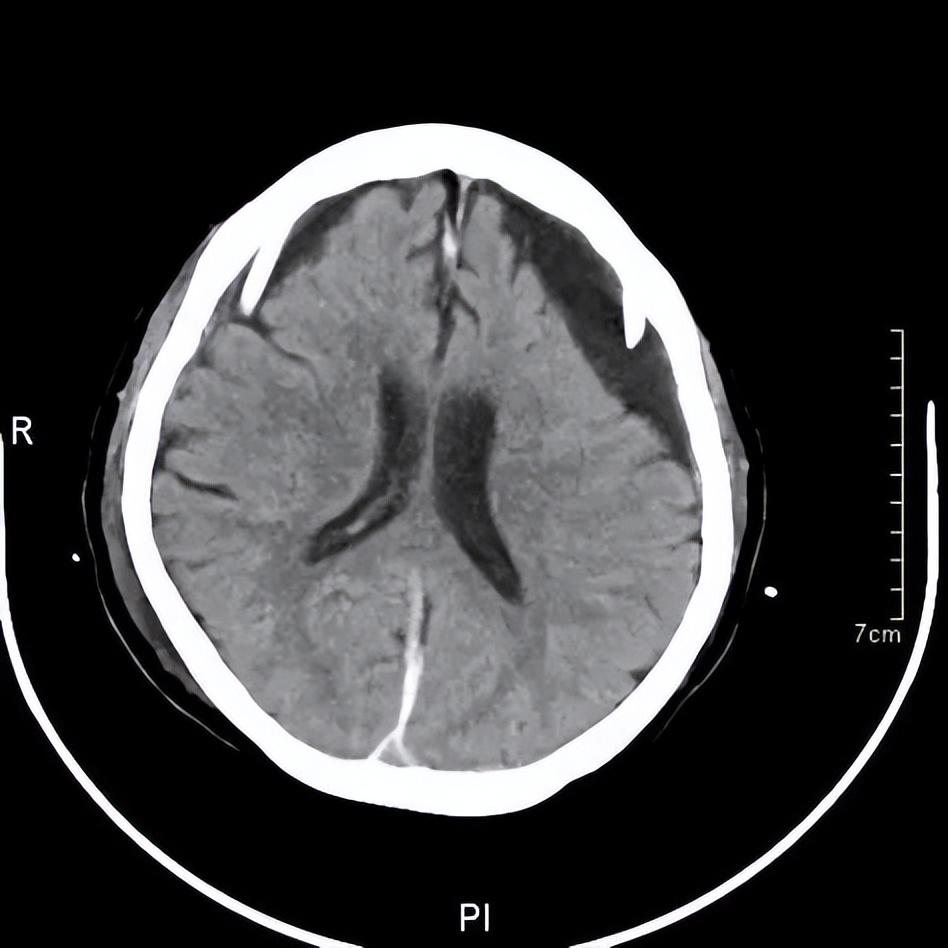

王阿婆手术后引流置管状态的头颅CT

最终王阿婆在我院神经外科接受了双侧钻孔引流手术。通过几天引流后,她就可以下床走动,说话也清楚了,记忆力也恢复了。她的儿女都很高兴,感谢黄主任和神经外科的医生们。王阿婆出院回家继续休养康复。几个月后复查,血肿完全消退,阿婆又恢复了昔日神采,一家人共享天伦之乐。